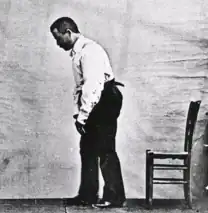

A. 1880s illustration of Parkinson's disease (PD) B. Mild motor-predominant PD C. Intermediate PD D. Diffuse malignant PD | |

Bradykinesia describes difficulties in motor planning, beginning, and executing, resulting in overall slowed movement with reduced amplitude that affects sequential and simultaneous tasks.[22] Bradykinesia can also lead to hypomimia, reduced facial expressions.[21] Rigidity, also called rigor, refers to a feeling of stiffness and resistance to passive stretching of muscles that occurs in up to 89 percent of cases.[23][24] Postural instability typically appears in later stages, leading to impaired balance and falls.[25] Postural instability also leads to a forward stooping posture.[26]

Beyond the cardinal four, other motor deficits, termed secondary motor symptoms, commonly occur.[27] Notably, gait disturbances result in the Parkinsonian gait, which includes shuffling and paroxysmal deficits, where a normal gait is interrupted by rapid footsteps—known as festination—or sudden stops, impairing balance and causing falls.[28][29] Most PD patients experience speech problems, including stuttering, hypophonic, "soft" speech, slurring, and festinating speech (rapid and poorly intelligible).[30] Handwriting is commonly altered in Parkinson's, decreasing in size—known as micrographia—and becoming jagged and sharply fluctuating.[31] Grip and dexterity are also impaired.[32]